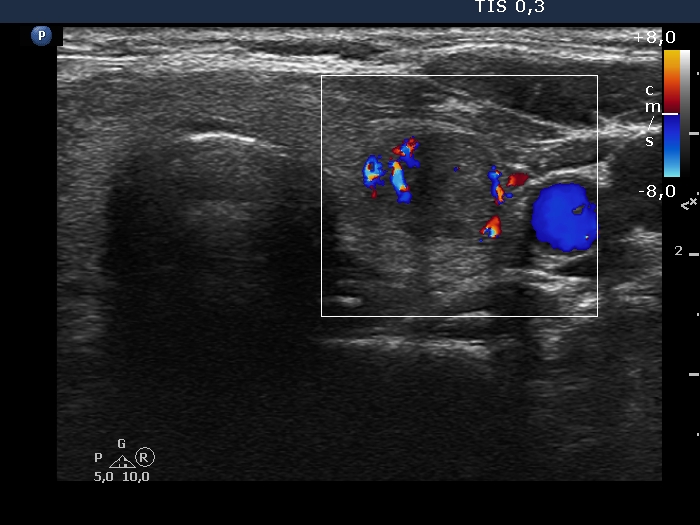

100 consecutive cases of papillary cancer - case 089 (ultrasonographic picture 6)

Right lobe, longitudinal scan

Left lobe transverse scan, color Doppler mode. The lesion has perinodular vascularity.